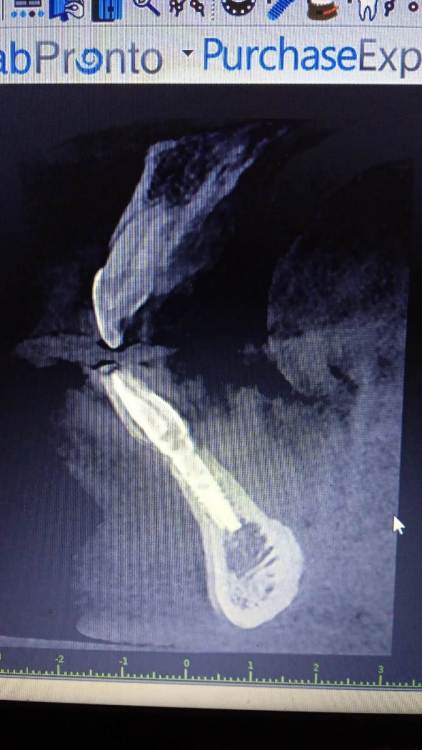

Jurai Опубликовано 25 декабря, 2016 Поделиться Опубликовано 25 декабря, 2016 *Предупреждение: фото на "мыльницу", не все этапы удались, но я работаю над этим) Вот пациент. Приятнейший, во всех отношениях, с негативным отношениям к мостовидным конструкциям. Полтора года лечил 41з по поводу периодонтита: толку не вышло. Удалил у широко известного многим стоматологам, особенно выпускам последних годов, доктора с ученой степенью. После удаления 4 месяца, по КТ область вполне достойно выглядит. Вот с чем пришел, обычное дело, все прилично: Раскрываю, а там между тонкими кортикалками мягко и упруго - резидуальная, фото нет. Открываю сильнее чем обычно, с расстройства не особо удачно. Кюретаж : Вид после, ушла вестибулярная кортикальная вместе с кистой: Сверлим 2,0, позиционердля рентген-контроля Имплантат ADIN UNP2,75Х11,5мм Ауто, джейсон коллагенфлис (что было под рукой) Швы. Контроль, перещелкивать не стали. В общем, понравился имплантат, для себя пометку кюретажить тщательнее, не надеяться, что организм все переварит. 1 9 Ссылка на комментарий